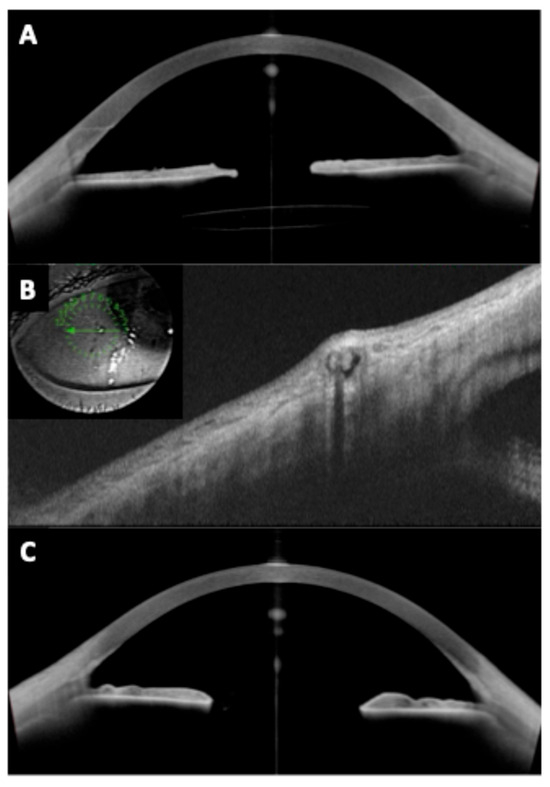

Background and Objectives: Optic disc drusen (ODD) can mimic papilledema and are linked to structural crowding, microvascular change, and visual-field loss. We synthesized structural/microvascular differences, functional status and change, diagnostic...